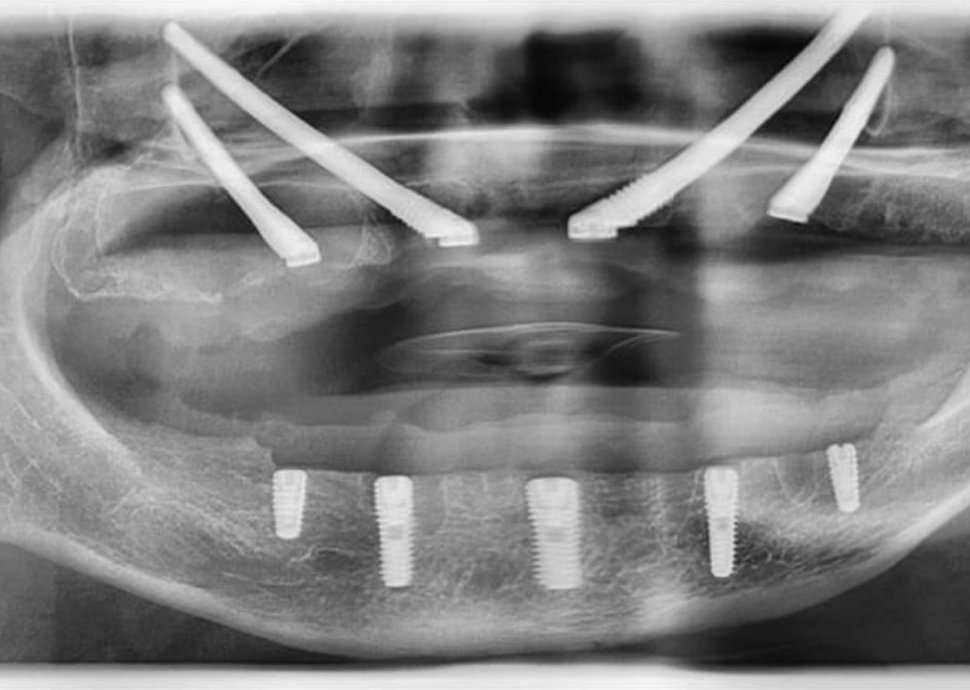

Der Prozess beginnt mit einer umfassenden Beratung, einschliesslich 3D-Scans (CBCT) und einer oralen Untersuchung zur Beurteilung der Knochengesundheit und der Eignung. Dieser Schritt dauert etwa einen Tag und ermöglicht die Entwicklung eines individuellen Behandlungsplans. In dieser kritischen Phase wird Ihr Chirurg die Anamnese erheben, eine detaillierte orale Analyse durchführen und basierend auf Knochenniveau und -anatomie Scans oder 3D-Röntgenaufnahmen durchführen – um die Eignung des Patienten für eine Implantation zu prüfen. Dies führt zur Erstellung eines individuellen Behandlungsplans.

Sobald der Behandlungsplan bestätigt ist, können die Implantate oft noch am selben oder am nächsten Tag eingesetzt werden. Der chirurgische Eingriff ist minimalinvasiv und dauert in der Regel 1 bis 2 Stunden, abhängig von der Anzahl der Implantate und der Komplexität des Falles. Dies ist eine wichtige Phase des Eingriffs. Nach dem vollständigen Abklingen der Lokalanästhesie, die einen Bereich betäubt, wird das darunterliegende Gewebe des Kiefers vorbereitet und die Implantate eingesetzt. Der chirurgische Eingriff dauert durchschnittlich nicht länger als zwei Stunden. Es wird die schonendste Methode angewendet, um Implantate in die Alveole fehlender Zähne einzusetzen, da das alleinige Ziel des Eingriffs darin besteht, Gewebeschäden und behandlungsbedingte Schmerzen zu minimieren. Daher wird der Patient während des Eingriffs unter Lokalanästhesie gesetzt und verspürt nach dem Eingriff kaum Beschwerden, bis die Narkose nachlässt.